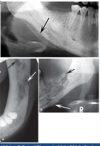

Q

what is this superimposition?

A

maxillary antrum

17

18

zygomatic buttress

19

mental foramen